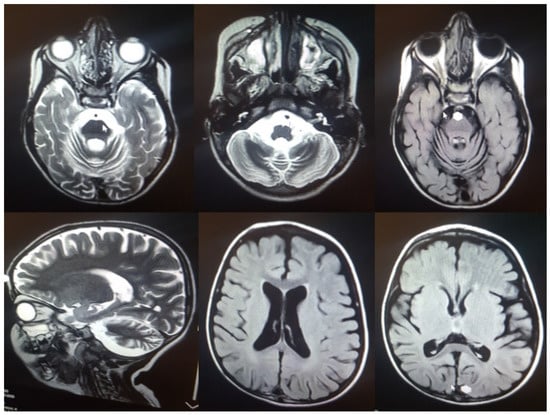

| 5y/M | Seizures/4y | Cerebellar atrophy, ataxia, epilepsy, vision loss, spasticity, tremor, motor difficulties, swallowing problems, sleep disorder, cognitive decline, language regression | yes | c.C832T | p.Q278X | 7 | PVS1, PM2 | LP | Hom | Iran | This study |